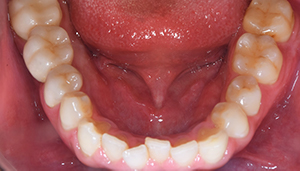

症例1

治療前

治療後

治療内容

口腔内の銀歯を全てセラミックにしたいというご希望でした。親知らずは抜歯しています。笑ったときや自然なスマイルをしたときも銀歯が見えなくなり自然になりました。

治療期間 約2ヶ月

治療費 合計:935,000円 (内訳)

オールセラミック:110,000円×5本

セラミックインレー:55,000円×7本

治療のリスク・副作用 銀歯の下で虫歯が大きくなっていたら歯の中の神経をとらないといけないことがあります。また、被せ物を外すと、ご自身の歯が少ない場合は別途はを残すための処置が必要になることがあります。